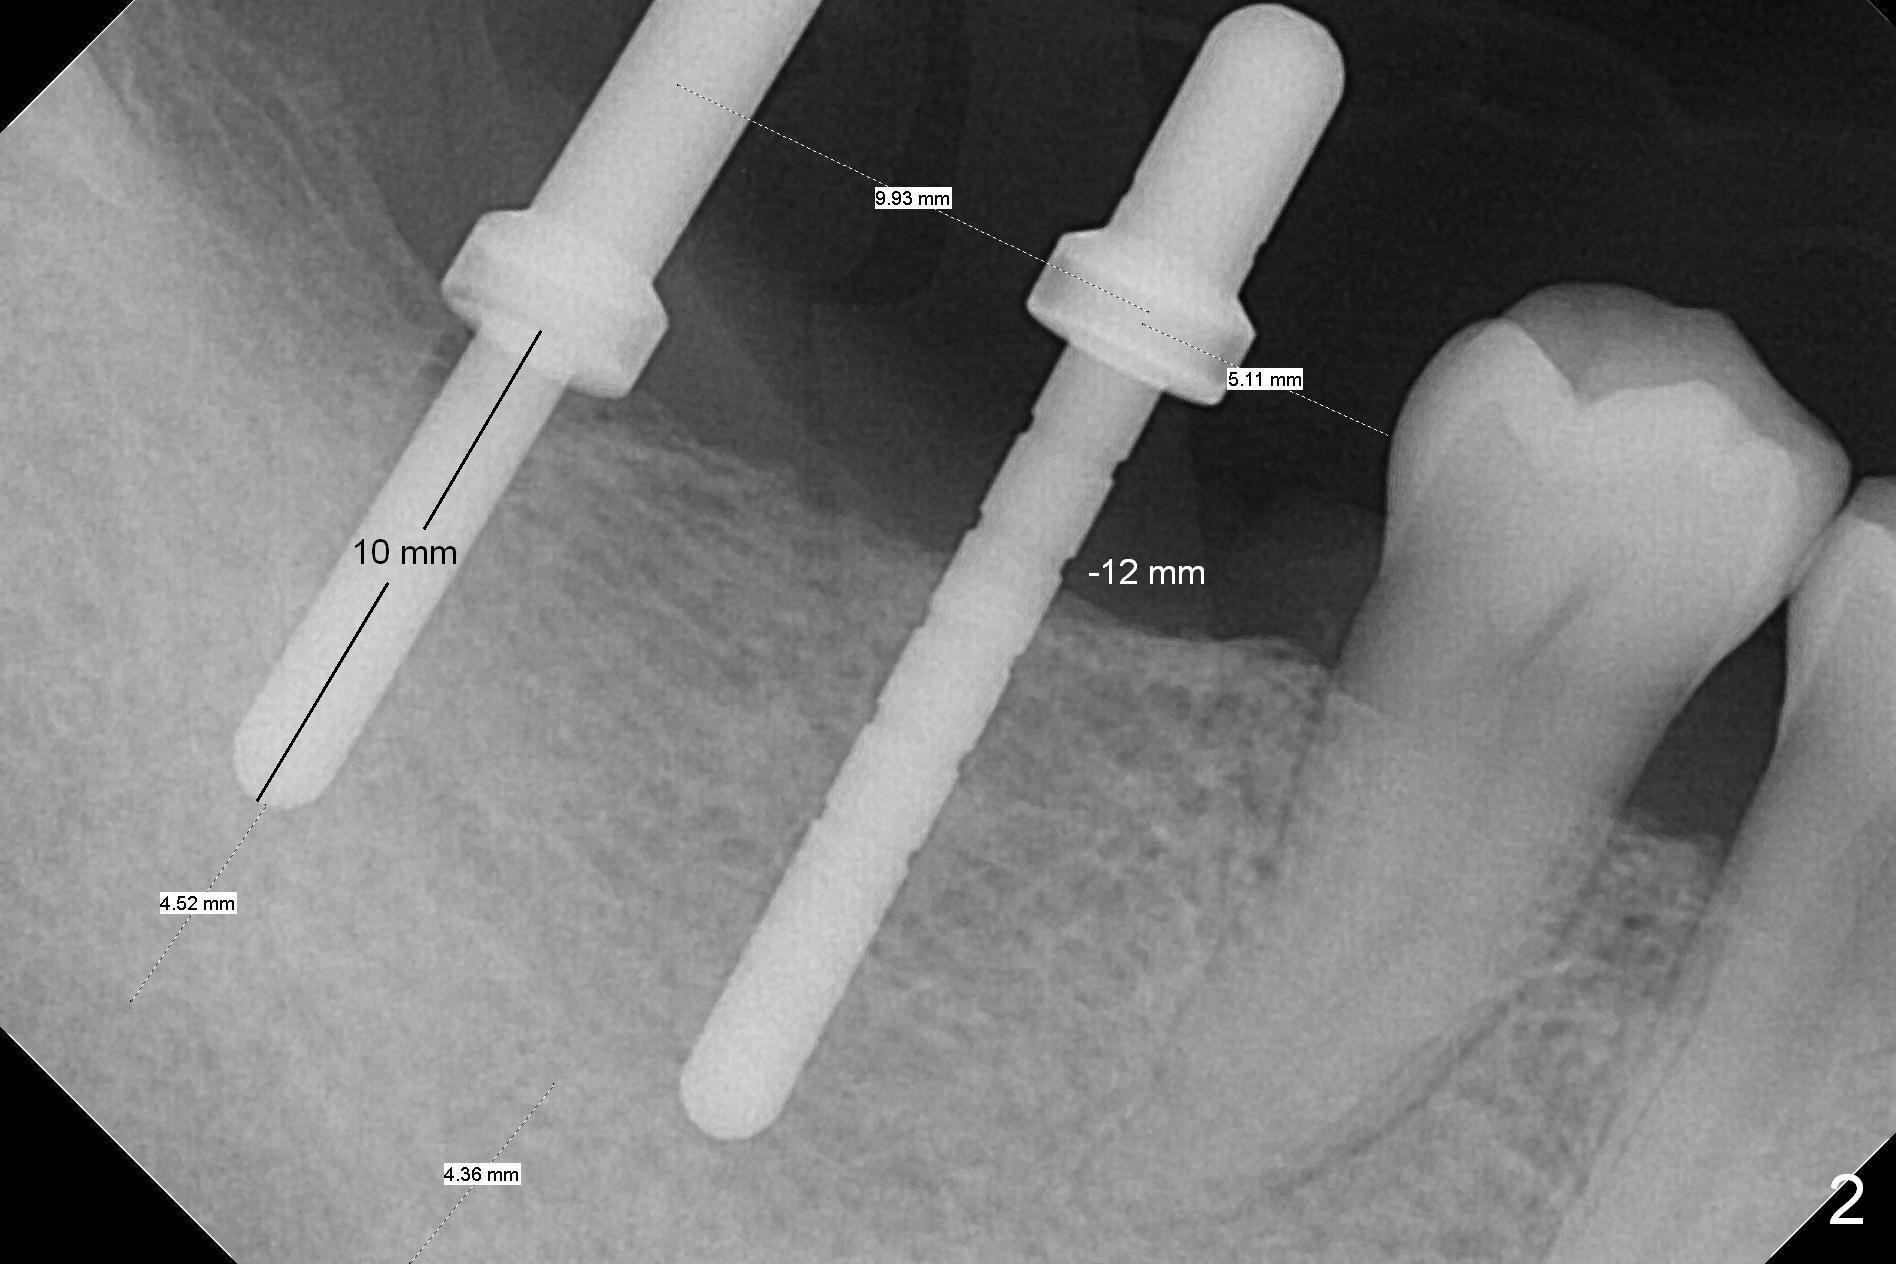

The supraerupted tooth #2 is adjusted using the lower right surgical stent.  Osteotomies are initiated by using starter drill through surgical stent over the ridge (Fig.1) prior to incision.  The initial depths are 10 and 12 mm at the sites of #31 and 30, respectively (Fig.2).  The new sensor with the existing sensor holder cannot reach the deep portion of the lingual vestibule (Fig.2,3).  Without the sensor holder, the #2 sensor with rounded corners has no problem showing the Inferior Alveolar Canal (Fig.4 red dashed line).  The two implants (5x12 and 5x14 mm, Fig.5) are placed with >50 Ncm.  Cemented abutments are immediately placed (6.8x4(2) and 6.8x4(3) mm) to reduce suture tension (after autogenous bone graft and collagen dressing) and hold periodontal dressing in place.  The wound does not heal completely 15 days postop (Fig.6).  The patient reveals that he smokes 1/2 pack per day.  There is crestal bone resorption 4 months postop (Fig.7 *).  It appears that for smokers, implants should be smaller, placed deeper and buried.  In addition, his oral hygiene is not good.